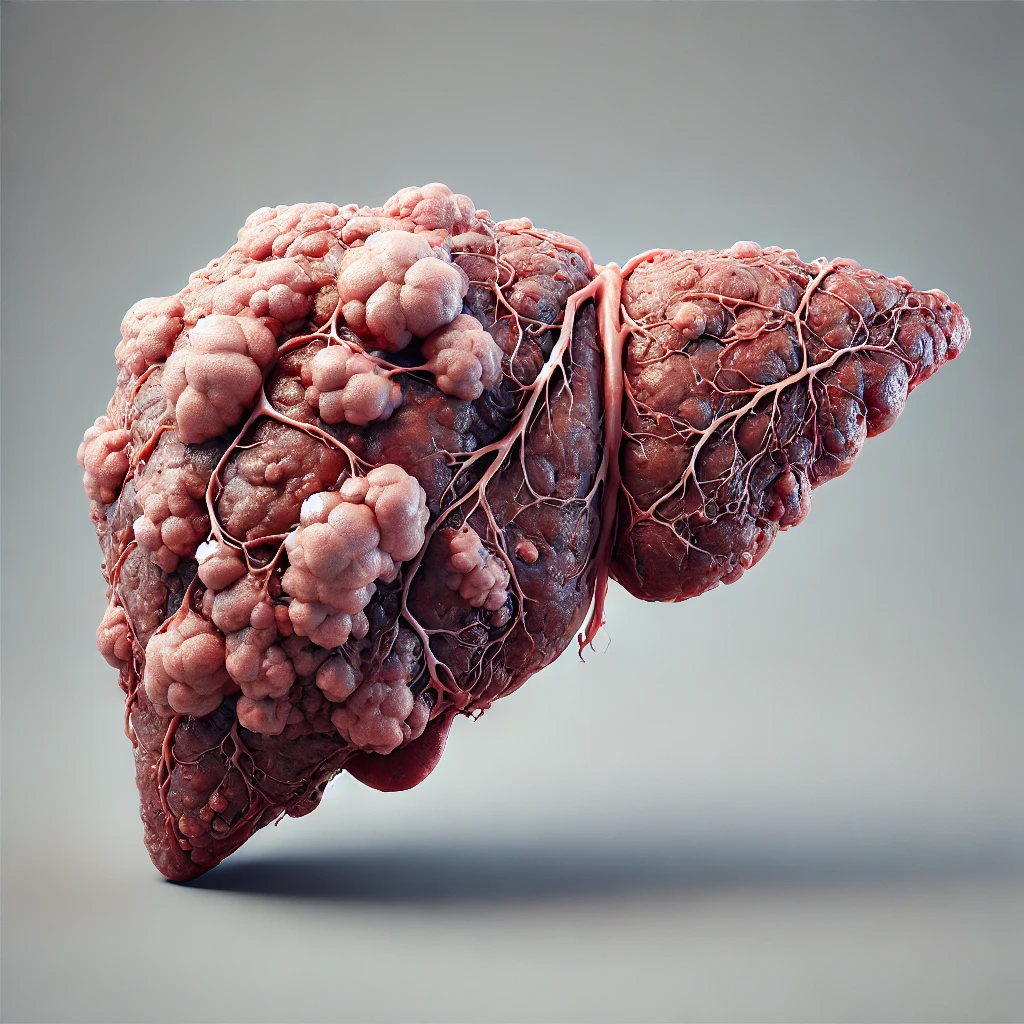

Veja a evolução da gordura no fígado não tratada.

A gordura no fígado não tratada pode evoluir de forma gradual. Inicialmente, ocorre a esteatose hepática (fígado gorduroso), onde há acúmulo de gordura nas células do fígado. Se não for tratada, pode progredir para esteato-hepatite não alcoólica (NASH), caracterizada por inflamação no fígado. Isso pode levar à fibrose hepática, com formação de cicatrizes no fígado, e, se persistir, evolui para cirrose hepática, onde o fígado perde a capacidade de funcionar corretamente, podendo resultar em insuficiência hepática ou até câncer de fígado. O tratamento precoce pode evitar essa progressão, geralmente com mudanças no estilo de vida.

Cirrose

A cirrose é o desfecho de lesões no fígado que se cicatrizam, fazendo com que o órgão vá perdendo sua função e caminhe para a falência completa.

Cancêr no Fígado

O câncer de fígado geralmente começa como um nódulo isolado ou como nódulos múltiplos no interior do órgão. Nas fases iniciais, o crescimento costuma ser lento e assintomático.

Evolução da esteatose hepática.